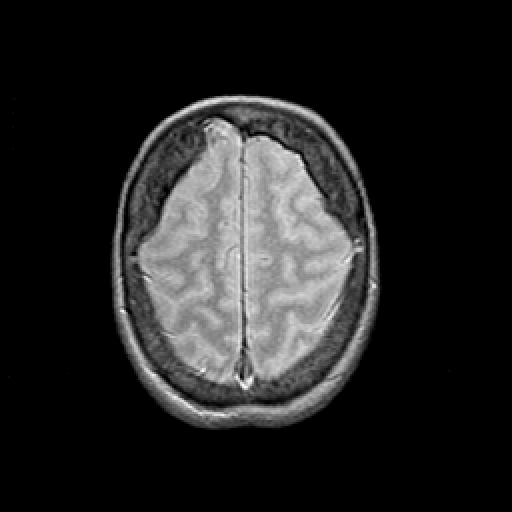

Proton density-weighted structural MR: Slice 43

Slice 43